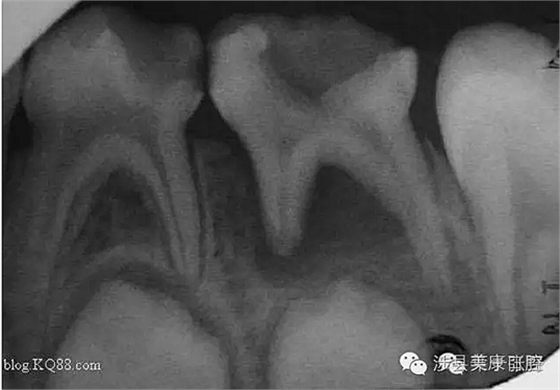

普通家長看了這張牙片估計(jì)能看出來孩子的牙不好,但是究竟不好到什么程度呢,讓葉子姐告訴大家:

上圖孩子的乳牙感染已經(jīng)將下面骨感染到吸收消失,并且直接影響到了下面的恒牙胚,家長們上點(diǎn)心吧。那些說乳牙不用治療,換牙就會(huì)好的人(包括醫(yī)生)還是睜開眼睛看看吧,不要自欺欺人,更不要用自己的錯(cuò)誤誤導(dǎo)他人誤導(dǎo)大眾。

網(wǎng)友又不明白了,什么叫吸收消失?看x片看不懂哎......

黑色部分表示那里的骨頭感染已經(jīng)爛沒有了,消失了,牙胚應(yīng)該在健康頜骨里孕育生長發(fā)育,現(xiàn)在在感染的病灶里生長,在膿水里侵泡。

又有好奇網(wǎng)友問他怎么有那么多牙?

乳牙下面有恒牙孕育著。